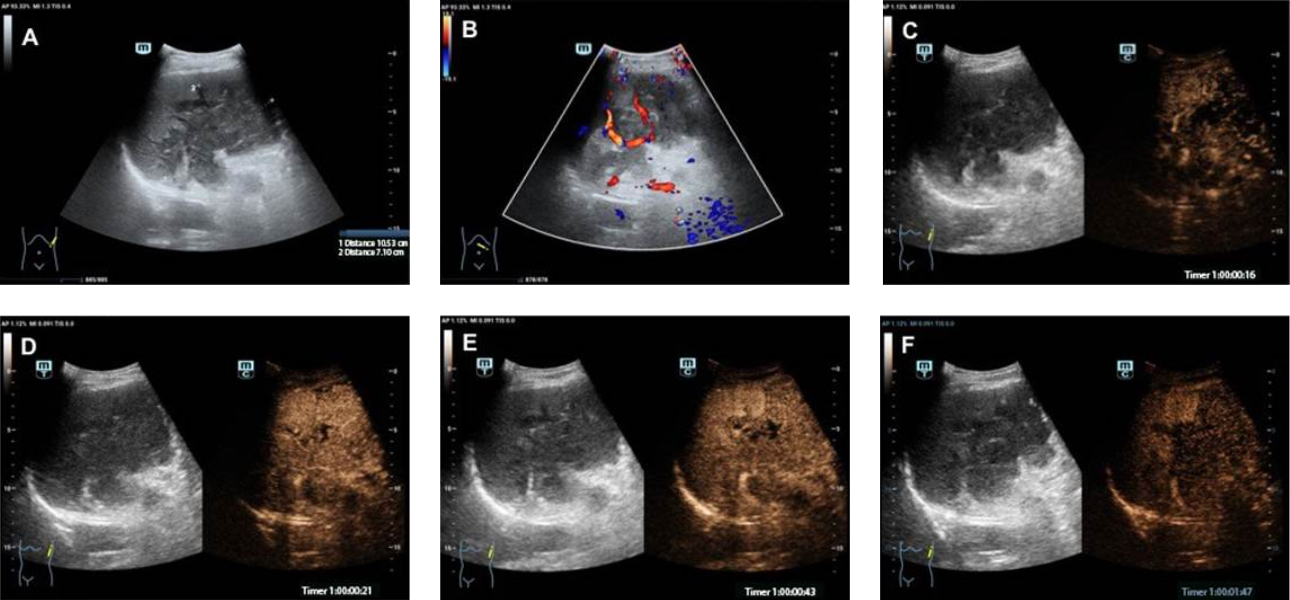

64?? ? ??? ?? ?? ???(left upper quadrant) ???? ????? ????? ??? ????? ??? B ?? ???? "???? ????? ???(heterogeneous hypoechogenicit) ? ?? ?? ?? ?? "? ?????. ?? ??? ?????? ??? CT? MRI ??? ?? ?? ?? ????, ??, ?? ?? ???????. ???? ???? ? ?, ?? ??, ?????(TMs) ??? ?? ???????. ??? ?? Zhejiang ?? ???? ?2 ?????? ??? ?? ??? ?????.

??? US, CEUS, CT ? ?? PET/CT ??? ???? ? ??? Fig 1-3? ????.

?? ????, Resona ???? ??? CEUS ???? Pintong ??? ?? ?? ? ?? ??? ?? ???? ??? ???? ???? ? ?????. ? ????, CEUS ???(delayed phase)? ?? ??(sieve-like) ??? ??? ??? ?? ???? CEUS ??? ??? ?? ???? CEUS ??? ??? ??? ? ? ????. ?? ??? ??? ????(Ultra-guided biopsy) ?? ??? ???(exploratory laparotomy)? ?? ?????? ??(histopathological examination)? ?? ??? ? ????.